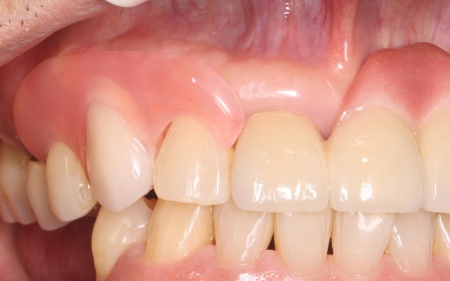

治療前

治療中

治療後

| 診断 | 拝見したところ、右上の犬歯には被せ物が装着されていました。 被せ物が装着されていると、レントゲン検査で歯の内部の状態を正確に確認することは困難です。 そこで、原因を詳しく調べるため被せ物を慎重に取り外し歯の内部を確認したところ、歯根が縦方向に割れる「歯根の垂直破折」が認められました。 また、このまま放置すると痛みや腫れが悪化し周囲の組織にも影響が及ぶ可能性があるため、抜歯が必要ですが、歯を抜いたままにすると隣の歯が動いて噛み合わせや歯並びに影響が出るおそれもあります。 以上のことから、抜歯したあとに歯を補う治療が必要と診断しました。 |

| 行ったご提案・治療内容 | 抜歯後に歯を補う方法には、欠損歯の両隣の歯を支えにして歯を補うブリッジ・インプラント・入れ歯の3つの治療法がありますが、患者様の場合、右上の犬歯の両隣の歯は治療されているためブリッジによる治療は困難です。 そこで、インプラントまたは入れ歯による治療を提案しました。 ・インプラント ・取り外し式の部分入れ歯 患者様は当初インプラントを希望されたものの、治療期間が長くなることから「まずは入れ歯で様子をみたい」とバルプラストによる治療を選択されました。 まず、感染の拡大を防ぐために右上犬歯の抜歯を行い、歯ぐきや骨が安定するまで一定期間経過を観察します。 |